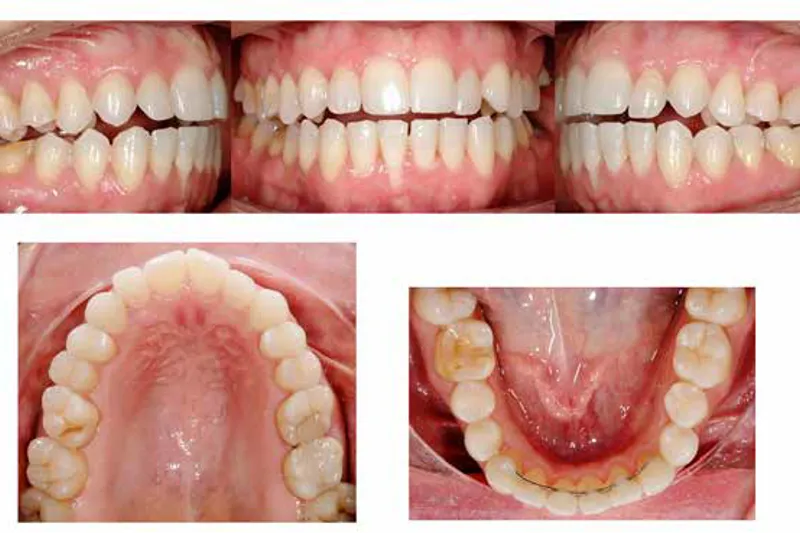

Tandregulering med gennemsigtige skinner har haft en eksponentiel vækst de sidste år. Skinnerne kaldes alignere og har revolutioneret især voksenortodontien de seneste 10-20 år. Tidligere var ortodonti et vanskeligt speciale at give sig i kast med uden officiel videreuddannelse i ortodonti, men med denne nye teknik på markedet er muligheden for praktiserende tandlæger blevet forøget. De fleste patienter kan lettere acceptere at blive behandlet med gennemsigtige plastikskinner end fast apparatur på tændernes forside. Øget tilgængelighed af teknikken og kraftige reklamefremstød kombineret med en øget efterspørgsel samt forskning og udvikling i feltet har gjort alignerne til en kommerciel succes, og markedet udvikler sig markant i disse år. Vi vil i denne artikel diskutere fordele og ulemper ved teknikken, belyse problemområder, informere om effektiviteten af alignere til specifikke tandflytninger samt illustrere effekten med to patienttilfælde. Artiklen er tænkt som en overordnet introduktion til den nuværende evidens omkring behandling med alignere, hvorefter den interesserede kliniker kan fordybe sig yderligere efterfølgende.

Orthodontic treatment with transparent aligners has had an exponential growth the last years. The aligners have revolutionized especially the adult orthodontic treatment during the last 10-20 years. Previously, orthodontics was a difficult specialty to embark on without a formal postgraduate orthodontic training, but this new technique has made orthodontic treatments available to general dentists. Patients have a lower threshold for accepting treatment using transparent aligners compared to buccal brackets. Increased availability of the technique and wide-spread commercialization combined with increased research and development have made the aligners a commercial success, and the market is developing significantly now. We aim in this article to discuss the pros and cons of the technique, address problem-areas, inform readers about the effectiveness of aligners for specific dental movements and illustrate this with two cases examples. The article is meant as an overall introduction of the current scientific evidence of aligner-treatment, preparing the interested clinician for subsequent further investigation.